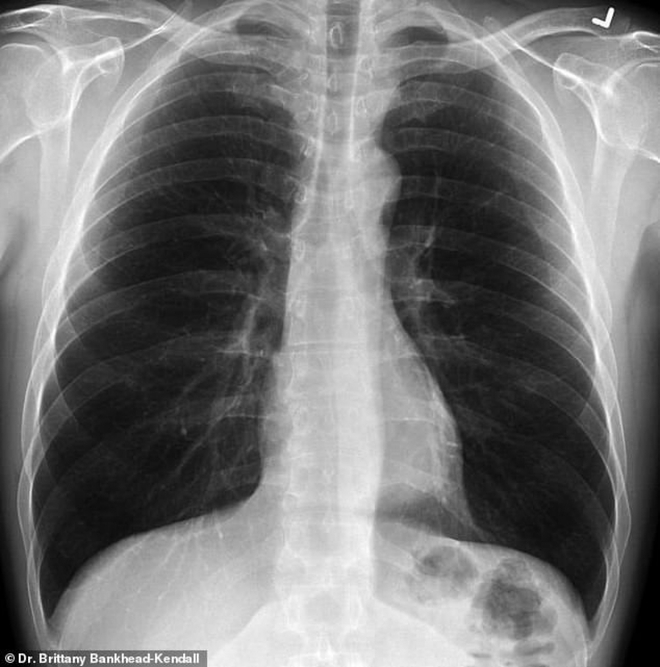

Phổi khỏe mạnh. Ảnh: Bác sĩ Kendall

Phim của người khỏe mạnh có nhiều khoảng đen, cho thấy họ có thể hít vào đủ lượng oxy cần thiết. Phim chụp phổi người hút thuốc thì có nhiều khoảng mờ, còn của bệnh nhân Covid-19 thì gần như trắng xóa.

Những khoảng mờ trên phim chụp phổi thường là chỉ dấu của dịch lỏng, vi khuẩn, hoặc tổn thương và vết sẹo.